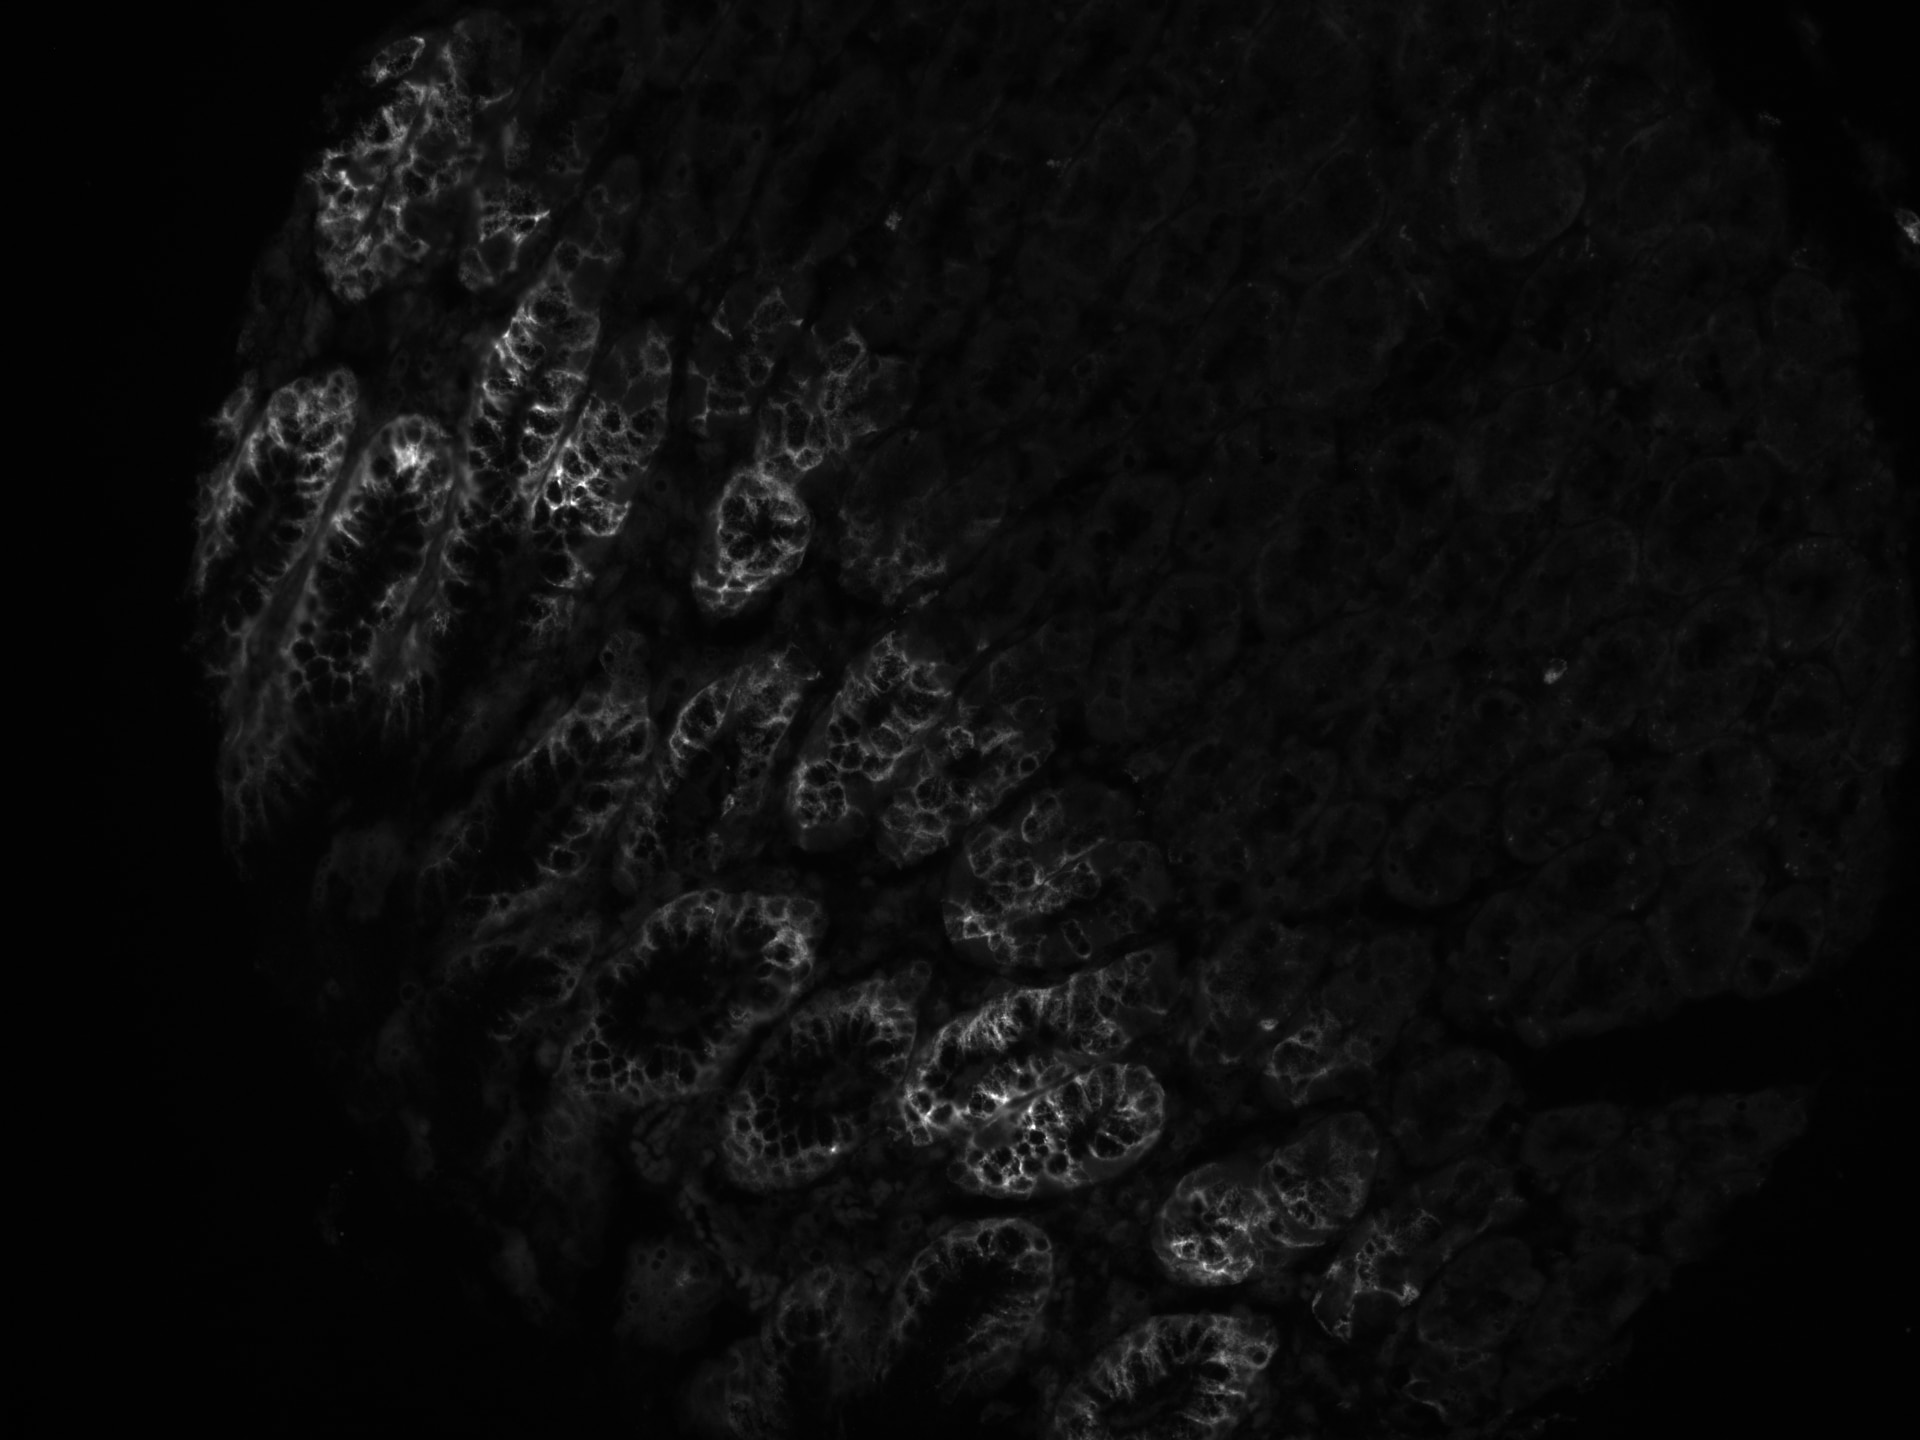

Immunocytochemistry/ Immunofluorescence: MUC5AC Antibody (CLH2) [NBP2-44455] - Human stomach tissue (FFPE). Antibody at 1:100. ICC/IF image submitted by a verified customer review.

Immunofluorescence - paraffin Human 03/07/2020

ApplicationOther

Sample TestedStomach tissue

SpeciesHuman

CommentspH9 antigen retrieval